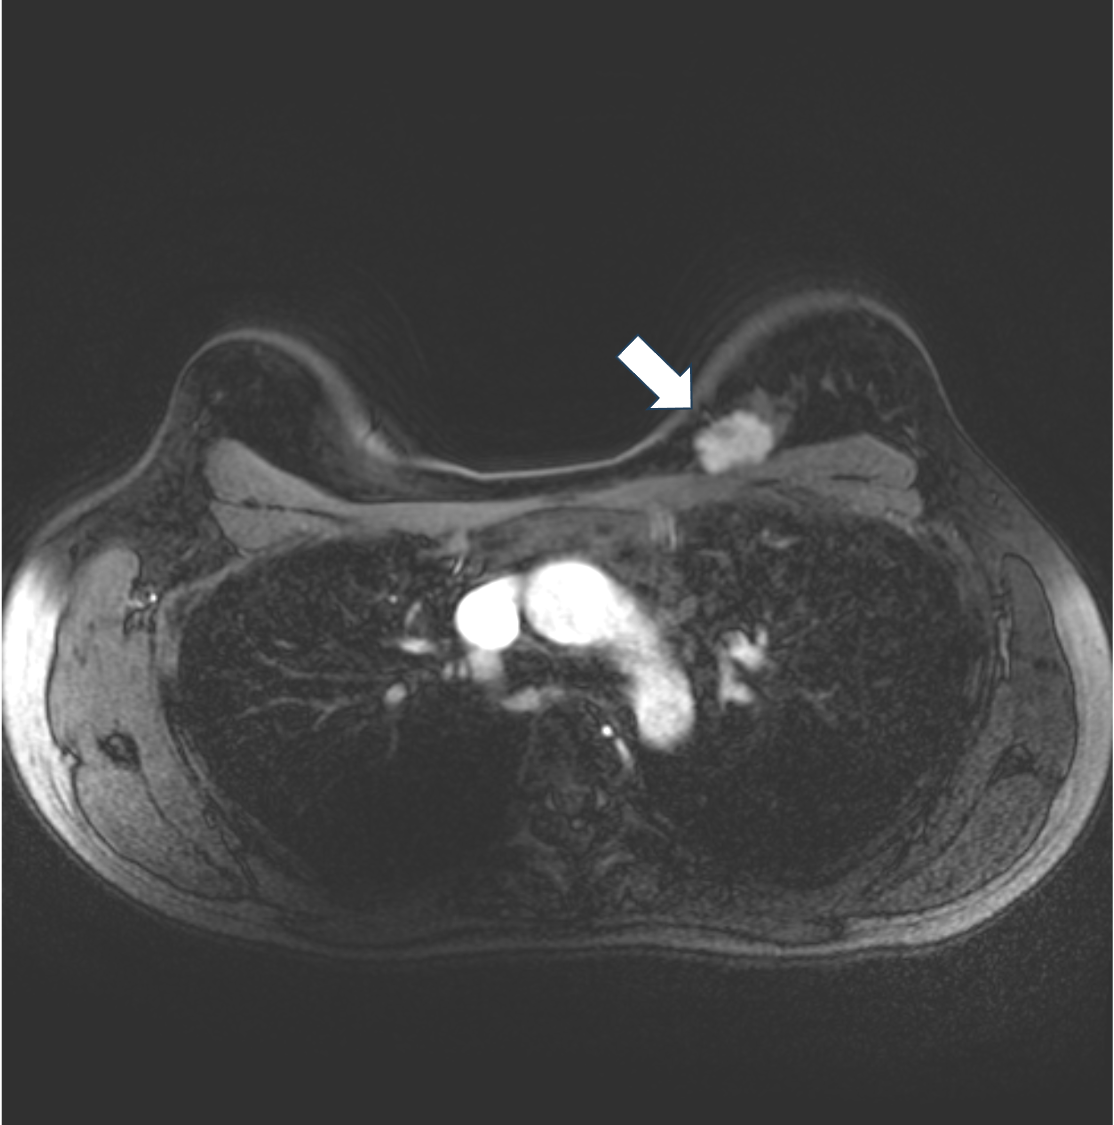

5. ダイナミックMRI 早期相

ダイナミックMRIでは不整形、境界不明瞭な腫瘤でfast-plateauパターンの不均一な造影効果を示す。